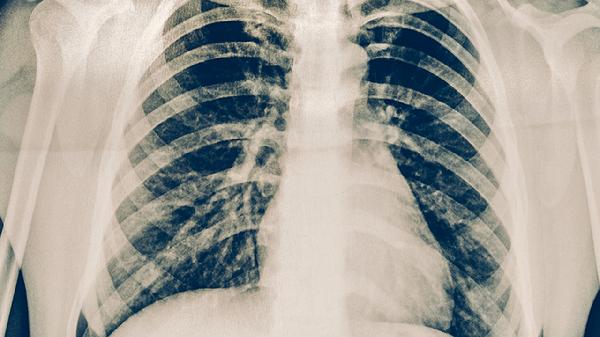

淋巴瘤确诊需依靠淋巴结活检、骨髓穿刺等检查,结合免疫组化分型。肺癌诊断主要依靠胸部CT、支气管镜活检、经皮肺穿刺等检查,病理确诊后还需进行基因检测。